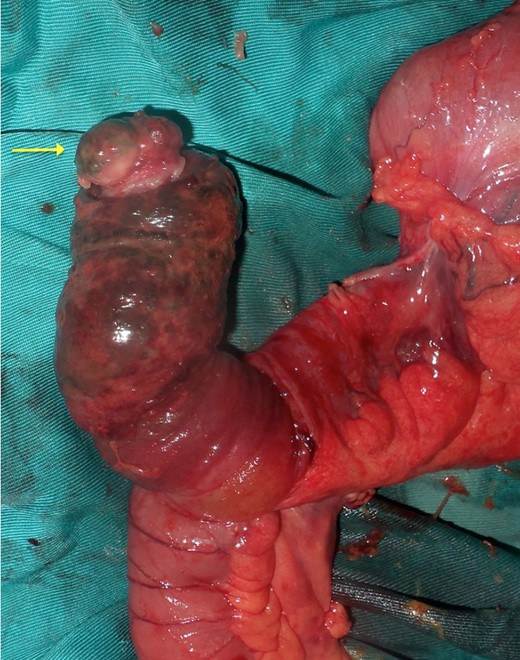

Upon laparotomy, we found an ileocecal intussusception, with mesenteric lymphadenopathies and a dilation of the whole small bowel (Fig. 3). We performed a right hemicolectomy, without attempting to reduce the intussusception, and an end-to-end ileotransverse anastomosis.

The post-operative outcomes were favorable. The pathological examination of the surgical specimen found an adenomatous ileal polyp with a high grade dysplasia on the terminal ileum being the cause of the ileocecal intussusception (Fig. 4).